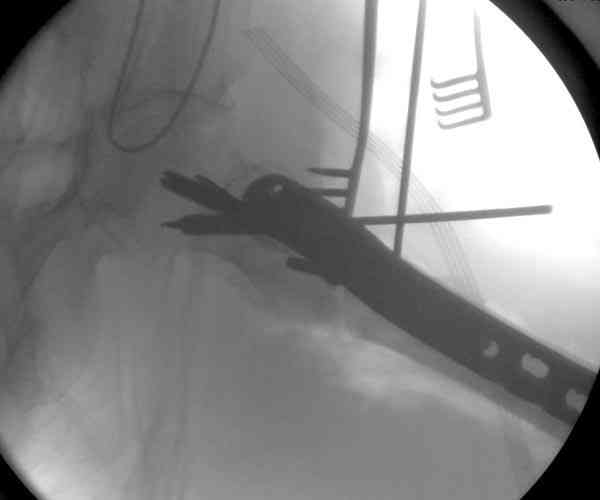

23.08.07г. на форуме был представлен больной 68 лет с диагнозом: несросшийся подвертельный косой перелом. http://www.weborto.net/forum/1187804790/ Больной после неудачной операции в одном районе в течении 7 месяцев был прикован к постели, с пролежнями в обл. крестца. Больной в течении 10 дней подготовлен к операции, НВ-153, эритр.-4,5, соэ-7, ВСК-3-3,40. ПТИ-81.ФНГ-3100. Мочевина, билирубин, АЛТ,АСТ в пределах нормы. Для остеосинтеза готовили пластину клинковую, штопор Сиваша . Во время операции дистальный отломок легко мобилизовали, проксимальный отломок был ротирован и сильно приведен медиально( m. iliopsoas), а также сильно замурован плотной как хрящ рубцовой тканью. Линия излома косая около 10 см., наружная стенка большого вертеля почти не было. У малого вертеля отсекли сухожилие m. iliopsoas и дальше на глубине начали распатором мобилизовать конец проксимального отломка, который был сильно приведен и находился глубоко , когда начали отделять изогнутом распатором заднюю часть конца и чуть подтянут отломка и тут начался сильнейшая кровотечения, фонтаном, найти сосуд и остановить кровотечение в ране не удалось, сосуд вместо с рубцовой тканью ушел назад и медиально отломка. Срочно рану туго тампонировали и остановили кровотечение, вызвали сосудистого хирурга,но их не нашли, оказалась один в отпуске, двое на экстренном вызове в районах. Передным доступом (по L. vasorum ) обнажали бедренную артерию, провели резиновую держальку и временно сосуд зажали, открыли рану , убрали тампон, но на глубине в толще рубцовых тканей поврежденный сосуд найти не удаётся. Поэтому переднюю рану расширили вниз, при ревизии бедренная артерия не повреждена, а глубокая бедренная артерия повреждена пристеночно, примерно на 2-3см от место отхождения от бедренной артерии, не доходя до ответвлений на огибаюших артерий. А одноимённая вена повреждена на протяжении около 3х см, и в данный момент восстановить не удается и пришлось перевязать оба конца, на артерию наложили поперечный сосудистый шов, бедренную артерию освободили, кровоток восстановился. Но теперь начала вся рана кровить! Венозный застой! К этому времени состояние больного резко ухудшилось, наступил клинический смерть, с трудом реанимировали, вроде б и кровотечение остановилось, как а/д подняли до 100/60мм опять начался кровотечение, коагулятором остановить не удаётся, рану туго тампонировали, перелито больше одного литра эр. массы и плазмы,и ешё кровозаменители, стабизол, рефортан и др. а/д держим 90/60, интесивная терапия против ДВС синдрома. Реаниматологи не разрешают производить остеосинтез, так как гемодинамика нестабильная , держиться под вазопрессорами. Через час состояние больного не улучшается , реаниматологи дали 10 минут и мы быстро кое как репонировали, остеосинтез продолной пластиной ЦИТО, но шурупы в проксимальном отломке плохо держутся, (остеопороз ), но другого выхода не было, для клинковой пластини просто небыло времени. Тканевое и капиллярное кровотечение продолжается, рану туго тампонировали и наводяшие швы на рану. Наложили гипсовой сапожок с деротатором. Больной находился в общей реанимационной отд. 20 дней и вышел из критического состояния. Но на контр. Р-грамме шурупы как и предпологали не держались, имеется ротация проксимального отломка, хотя ось бедра правильная и клинически деформации нет, даже определяется клиническая схватка . Я долго думал, вынести это на форум или нет, позвонил Челнокову А Н, он сказал <надо быть честным до конца, доложил на форуме, надо сообшить и о резултатах> Уважаемые коллеги! Какие были допушены ошибки? И какие рекомендации будут теперь? . P. S. за некачественный р-снимок прошу прошения!

Из-за ослабленного латерального кортекса в проксимальной части бедра (прорезавшийся первичный неудачный штифт) штифт для фиксации не годится. Потом для установки современных блокирующих штифтов необходимы дополнительные оборудования и опыт применения.

Адекватная фиксация достигается длинным 95 градусным Blade Plate, где клинок пластины, связывая головку со средней трети бедра, создал бы условия для сращения.

Другой вариант пластины, это Synthes Proximal Locking Plate предназначенный для лечения прксимальных переломов бедра, где три шурупа: два 7.3 мм, введенных в головку под углом 95, 120 и 5.0 мм в 130 градусов, создают угловую стабильность.

Профилактику прорезывания шурупов в кости можно добиться введением в отверстие цемента, потом проведением шурупа, цемент, застывая, удерживает шуруп в правильном положении.